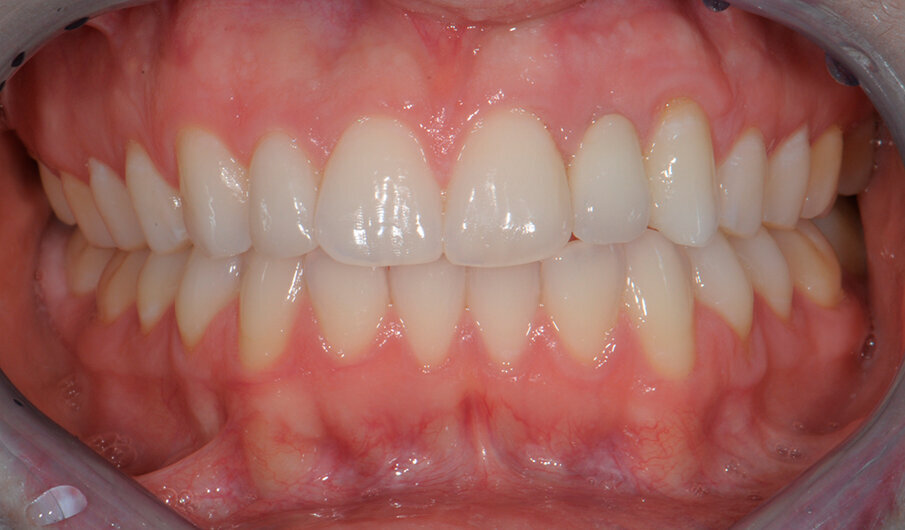

Fig. 2 - Foto inziali del caso. Si noti la presenza di elemento 12 di conformazione conoide e agenesia di elemento 22 sostituito con protesi tipo Maryland.

Fig. 6a - Corona cementata.

Fig. 6c - Controllo dei tessuti molli a un mese.

Fig. 8a - Caso concluso con veeners in ceramica a livello del 22.

Fig. 8b - Occlusione finale della paziente.